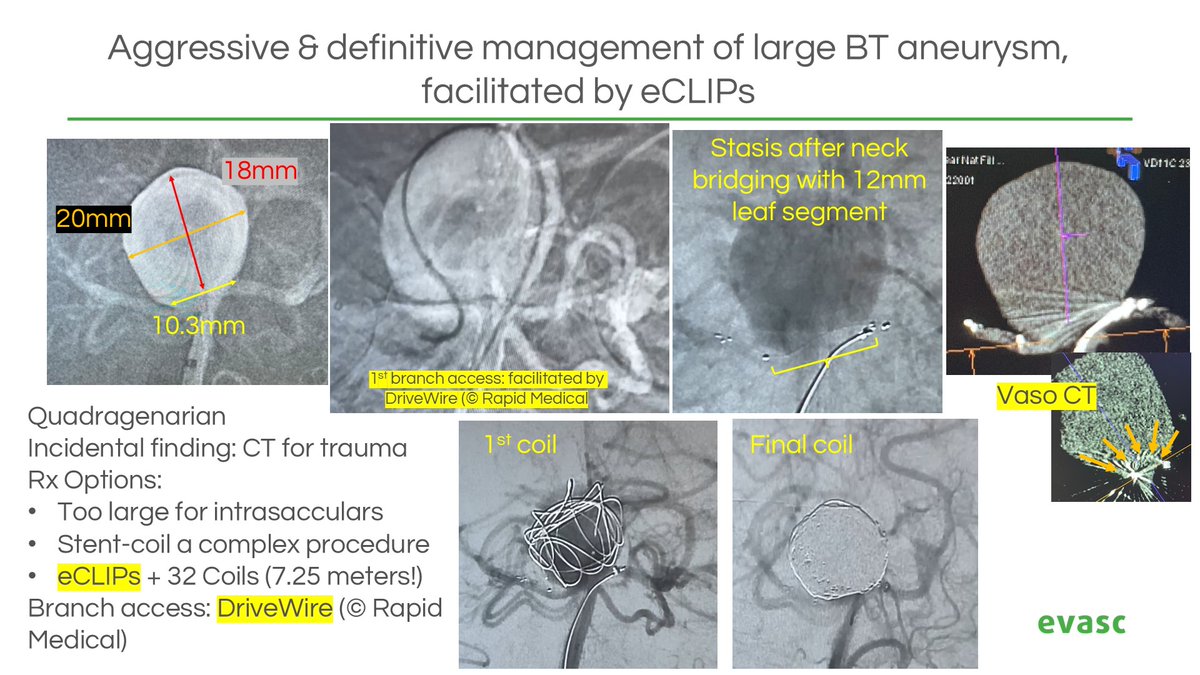

When intrasacculars fall short, #eCLIPs delivers. Massive BT #aneurysm treated with 725 cm of coils packed behind a 12 mm implant. Sidebranch access made possible with Rapid Medical steerable Drive Wire. Kudos to the team on this life-saving case! 👏 🔗bit.ly/contact-evasc

Adnan H. Siddiqui, MD SNIS Info Rapid Medical DriveWire assisted management of huge BT aneurysm, eCLIP'd with 12mm eCLIPs, and densely coiled